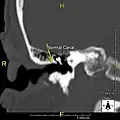

Normal ear canal

The normal ear canal is approximately 7 mm in diameter and has a volume of approximately 0.8 ml (approximately one-sixth of a teaspoon).[5] As the condition progresses, the diameter narrows and can even close completely if untreated, although people generally seek help once the passage has constricted to 0.5–2 mm due to the noticeable hearing impairment. While not necessarily harmful in and of itself, constriction of the ear canal from these growths can trap debris, leading to painful and difficult to treat infections.